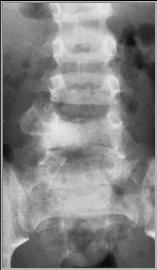

Location of lesion